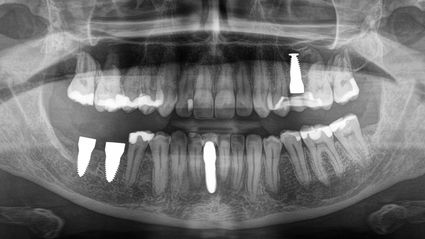

Meine Symptome, darunter Gelenkschmerzen, neurologische Probleme und Sehstörungen, nahmen trotz der Behandlung langsam aber stetig zu. Meine Symptome - vor allem die neurologischen - verschlimmerten sich, nachdem ich nach einem Zahnverlust und einer umfangreichen Wurzelbehandlung ein Titanimplantat erhalten hatte.

Ich besuchte die SWISS BIOHEALTH CLINIC im März 2019, nachdem ich alles über ihren ganzheitlichen biologischen Ansatz in der Zahnmedizin für Metallimplantate gelesen hatte, und wusste, dass dies ein neuer Schritt auf meinem Weg zur Gesundheit war. Unmittelbar nach der Entfernung des Titanimplantats begann sich mein Körper zu entspannen, die anhaltenden Schmerzen in meinem linken Ellbogen verschwanden und meine Sehkraft auf dem linken Auge kehrte zurück.